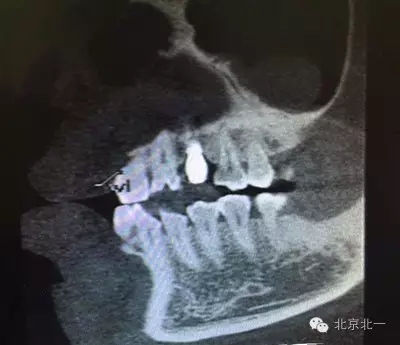

患者種植一月后種植區(qū)不適,偶有疼痛來院拍片發(fā)現(xiàn)23埋伏牙,與種植體相鄰,如圖一、二、三、四所示。

本病例建議:北一種植王明老師建議拔除埋伏牙,并同期植骨,觀察植體情況。提前告知患者失敗等風(fēng)險,簽署同意書。

但是國外文獻(xiàn)卻有不拔除埋伏牙的直接種植病例報告陳剛博士(本文獻(xiàn)由友睦齒科陳剛博士提供,向陳剛博士致謝。感興趣的醫(yī)生可去下載。)